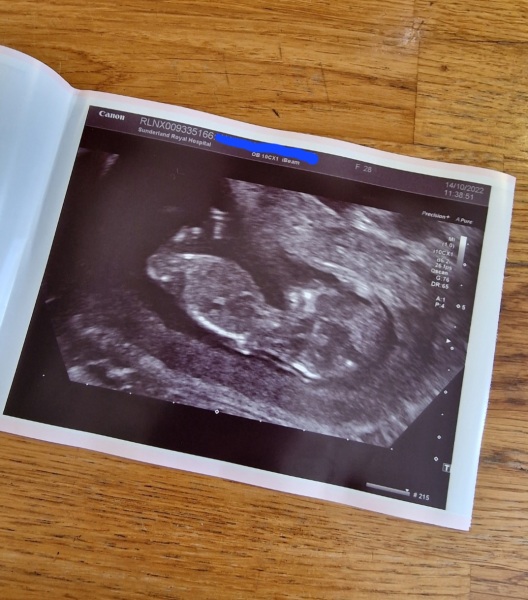

@MamaMenna lovely scan! I think girl 💗💞

Catching up from a few threads ago - wow things have moved fast! So lovely to see your scan pics and happy news. Hope everyone is starting to feel more human too! Had our 12 week scan last week and it's nice that all our family/friends knows! Any ideas as to boy or girl?? I'm useless at nub theory 🙈